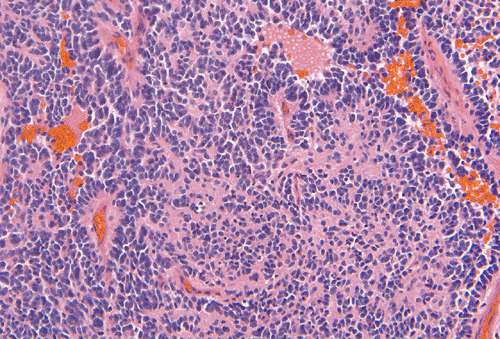

- Panel A: Medulloblastoma is typically a densely

packed, highly cellular small blue cells neoplasm with small and hyperchromatic nuclei. In contrast to medulloepithelioma,

the tumor cells arrange in solid sheets without forming any specific

pattern. This pattern is more reminiscent of the early but not earliest

stage of embryonal development of the central nervous system.

Occasionally, Homer Wright rossettes can be seen in medulloblastomas.

Mitotic activity is very brisk and many apoptotic bodies are also

present.